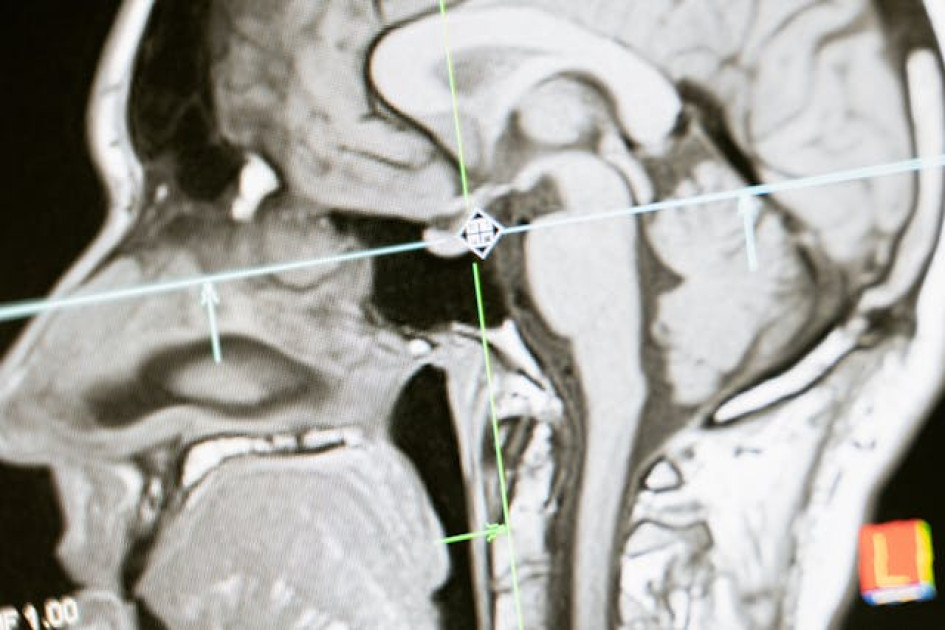

Foto | www.pexels.com | LA PATRIA | El cerebro evoluciona con el paso de los años. Sepa cómo lo hace.

La investigación, dirigida por neurocientíficos de la Universidad británica de Cambridge, se basa en datos de resonancias cerebrales de 3 mil 802 personas de entre 0 y 90 años, en las que se han mapeado las conexiones neuronales mediante el seguimiento del movimiento de las moléculas a través del tejido cerebral.